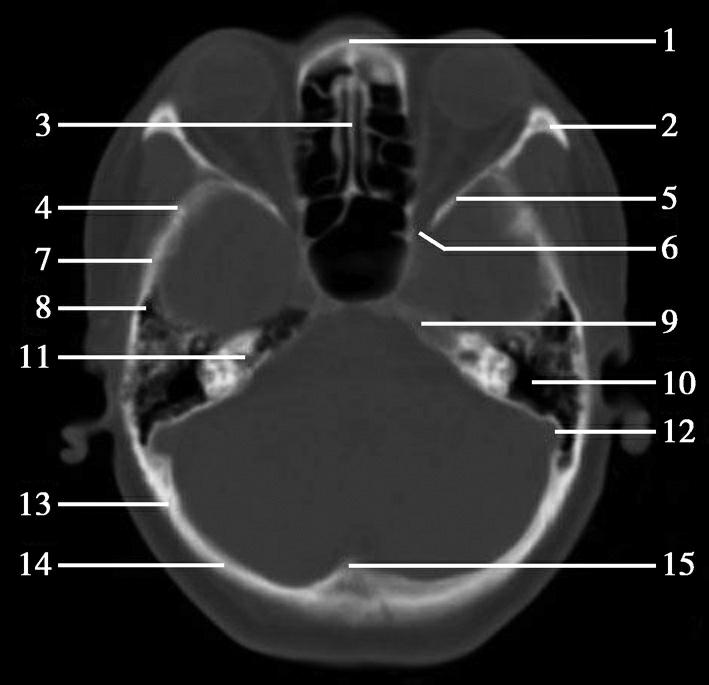

重要结构:卵圆孔、棘孔、破裂孔、斜坡、颞骨岩部、颈静脉孔(图1-2-1、图1-2-2)。

图1-2-1 颅底层面

A.横断面;B.横断面标注

1.晶状体;2.筛窦;3.颞肌;4.中颅窝底;5.外耳道;6.延髓;7.乙状窦;8.小脑半球;9.眼球;10.眼眶;11.上颌窦;12.蝶窦;13.乳突;14.耳郭;15.小脑蚓部;16.枕内隆凸

图1-2-2 颅底层面(骨窗)

1.鼻骨;2.筛窦纸板;3.颧骨眶突;4.翼腭窝;5.蝶骨大翼;6.卵圆孔;7.破裂孔;8.颞骨颧突;9.棘孔;10.斜坡;11.颞骨岩部;12.乳突;13.颈静脉孔;14.枕乳突缝;15.枕骨;16.枕内隆凸

层面前部呈开口向前的“V”字形,正中为鼻中隔,向两侧依次为筛窦和眼眶,眼眶内前部为眼球,后部为眶脂体。翼腭窝位于眼眶后部,窝内含有脂肪并有上颌神经通过。层面中部为蝶骨体,蝶骨体中部可见含气蝶窦,蝶窦后方为枕骨基底部,两者呈前后关系,其上面构成斜坡。蝶窦两侧为蝶骨大翼,其后外侧缘处由前向后可见卵圆孔和棘孔,分别有下颌神经和脑膜中动脉通过。斜坡外侧、岩骨尖前方为破裂孔。蝶骨大翼与眶外侧壁的颧骨借颧弓相连,颧弓和蝶骨大翼之间有咬肌及颞肌。层面中部外侧为外耳道。颞骨岩部呈“八”字形,相互之间借破裂孔软骨、蝶岩软骨结合和岩枕软骨结合连接。岩部后外侧的乳突部内可见乳突小房,乳突部与枕骨相接。岩骨后部可见颈静脉孔,内有颈内静脉、舌咽神经、迷走神经和副神经通过。层面后部为颅后窝,其内可见延髓,延髓前方为延髓前池,内有椎动脉,后外侧为小脑半球下部,后方为第四脑室、小脑扁桃体及小脑蚓部。

破裂孔、卵圆孔、棘孔及斜坡等均为重要的解剖结构,临床常见疾病如鼻咽癌常侵犯上述结构(图1-2-3)。颈静脉孔区较常见的肿瘤为颈静脉球瘤,常伴有颈静脉孔及其邻近骨质的破坏(图1-2-4)。